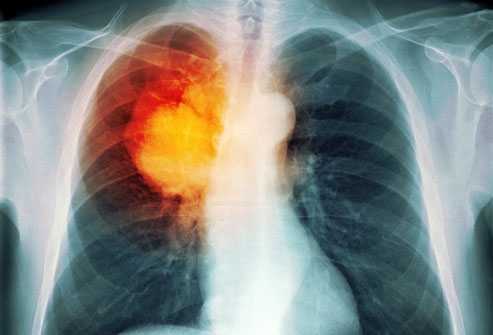

'Sát thủ' hàng đầu gây ung thư phổi

Ung thư phổi là căn bệnh nguy hiểm có tỷ lệ tử vong cao nhất trong các loại bệnh ung thư; theo các nhà khoa học và chuyên gia y tế, thuốc lá là nguyên nhân hàng đầu gây nên căn bệnh đáng sợ này.

Trong thế kỷ này, nếu không có các biện pháp phòng chống tác hại thuốc lá, thì khói thuốc sẽ giết chết 1 tỷ người, thông tin từ chương trình phòng chống tác hại thuốc lá quốc gia cho hay.